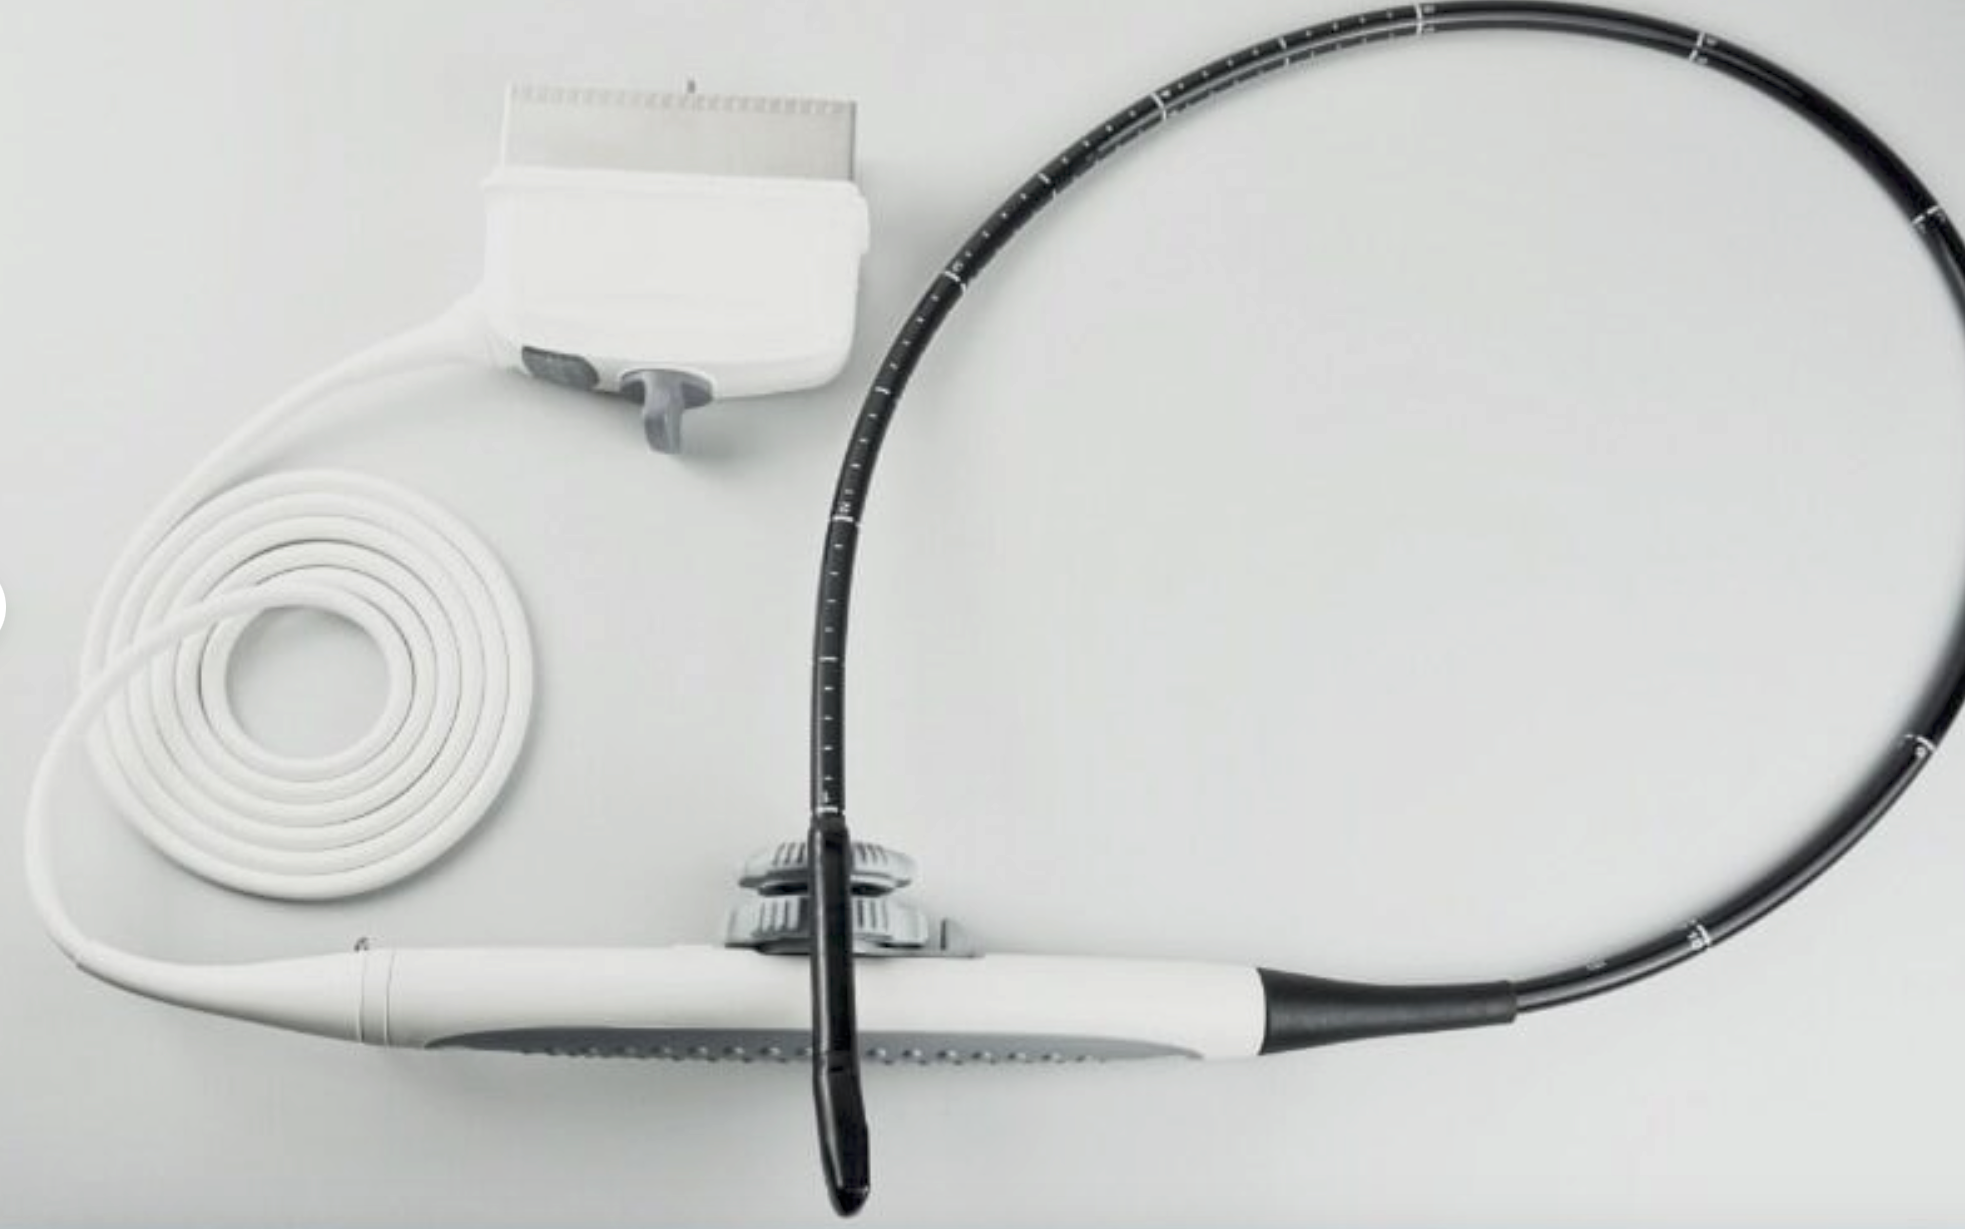

Handheld Ultrasound Scanner

Standard Configuration

Main unit (Transducer included): 1pc,USB wire: 1pc

Adapter: 1pc Carrying bag: 1pc Bag of gel(20g): 1pc |